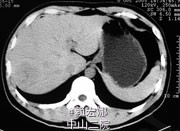

辅查:AFP 3.43ng/ml, CEA 1.47ng/ml。MR:肝S5段占位性病变(26*25mm),考虑肝癌可能性大,建议活检。

随访:术后病理示:(右肝肿物)送检肝组织部分呈结节状增生,结节间见粗细不等的纤维间隔,其内见血管增生,少量淋巴细胞及浆细胞浸润,符合肝局灶性结节状增生(FNH)。 讨论:肝局灶性结节增生(FNH)是肝内第二常见良性肿瘤,一般无临床症状,影像学表现,MRI上T1WI和T2WI与周围肝实质信号相近,增强扫描动脉期明显强化,若存在中央瘢痕,则中央瘢痕不强化,门脉期及静脉期强化程度减退,中央瘢痕则呈延迟强化。FNH需与肝癌和肝腺瘤鉴别,本例即误诊为肝癌,若存在中央瘢痕,则诊断较容易。